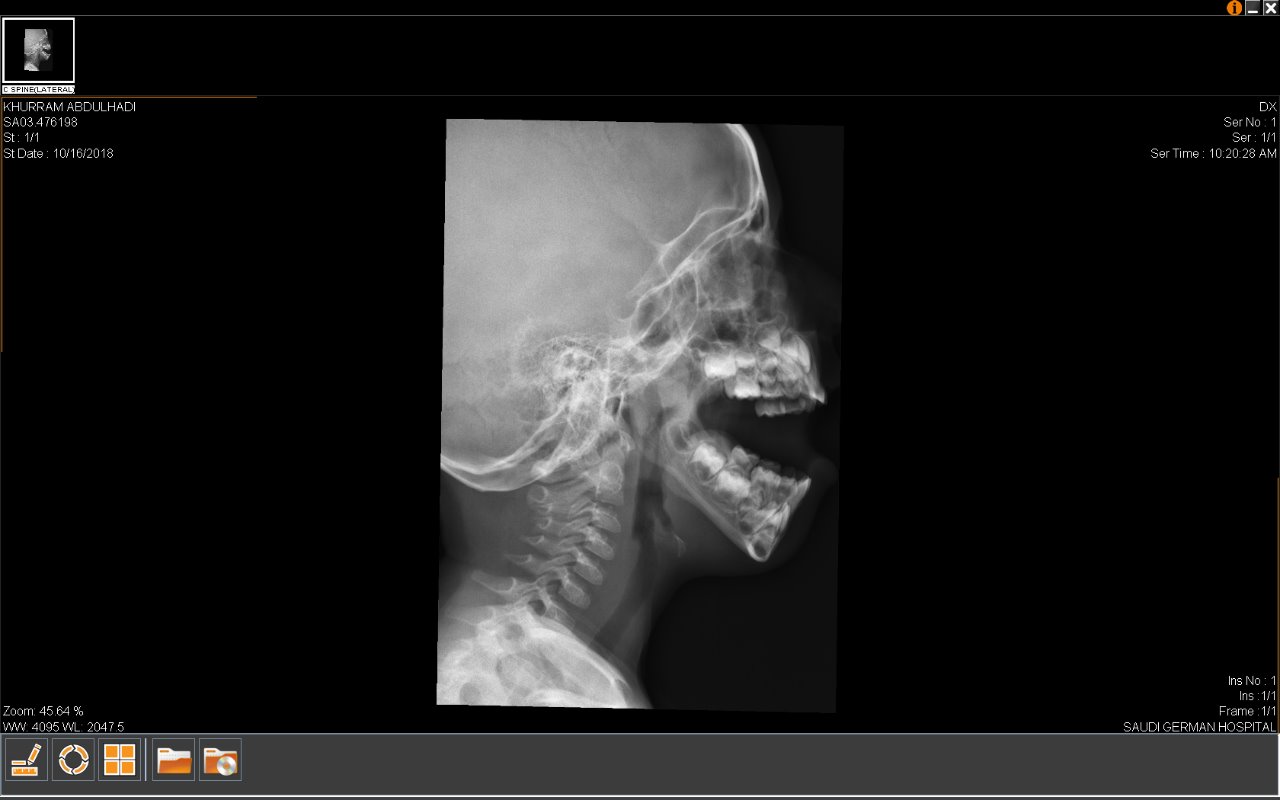

My son sleeps with mouth opened and a very little snoring voice can also be observed. Sometimes also have nasal voice. There was not any other serious symptoms that we had observed. I went for examination in different hospitals and they diagnosed Enlarged Adenoids and recommended us surgery Adenoidectomy. One doctor even advised me Ear Tube Surgery and Adenoidectomy both. I am very scared and confused to decide it. Kindly guide me, what should be the right action. Reports are attached for your reference.

X-ray is not taken in proper view n may need to be repeated . Moreover the nose needs examination. Anyway there is no need for any tube surgery. Better get appointment. Only then I'll be able to anything definitely. Dr Riaz

On reviewing a better film of ur child, there looks apparent enlargement of adenoids. adenoids surgery only is advised. Other tests are normal Dr Riaz